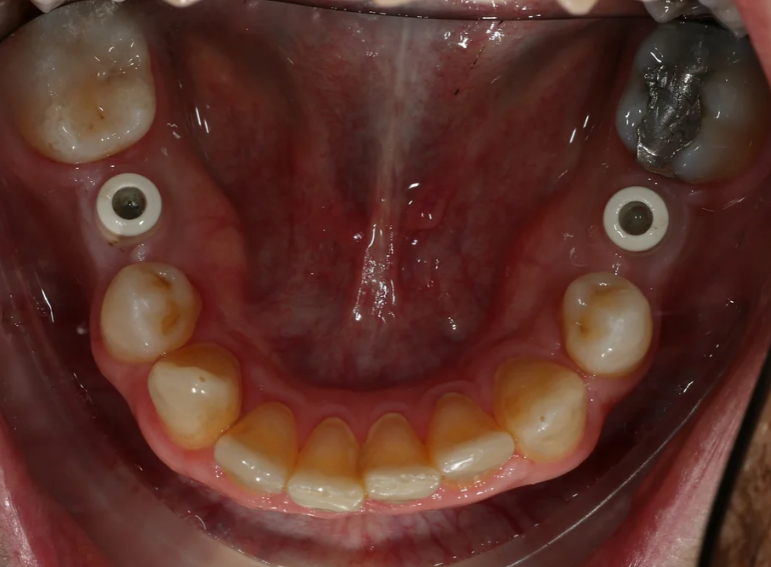

Case 9 – Implants

Placement of implants in a patient with hypodontia.